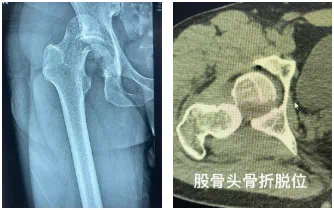

36岁的张先生(化名)因电动车追尾事故被紧急送往我院。右侧髋部剧烈疼痛、活动受限,右下肢短缩3CM,屈曲内收畸形。

影像学检查显示:右侧髋关节脱位、Pipkin IV型股骨头骨折及髋臼后壁骨折。

CT显示 股骨头骨折复位并不满意 ,需要手术 ,然而手术入路 、内固定方式又是问题。